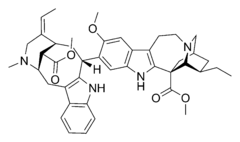

Dimer alkaloids

In addition to the described above monomeric alkaloids, there are also dimeric, and even trimeric and tetrameric alkaloids formed upon condensation of two, three, and four monomeric alkaloids. Dimeric alkaloids are usually formed from monomers of the same type through the following mechanisms:[193]

There are also dimeric alkaloids formed from two distinct monomers, such as the vinca alkaloids vinblastine and vincristine,[27][135] which are formed from the coupling of catharanthine and vindoline.[194][195] The newer semi-synthetic chemotherapeutic agent vinorelbine is used in the treatment of non-small-cell lung cancer.[135][196] It is another derivative dimer of vindoline and catharanthine and is synthesised from anhydrovinblastine,[197] starting either from leurosine[198][199] or the monomers themselves.[135][195]